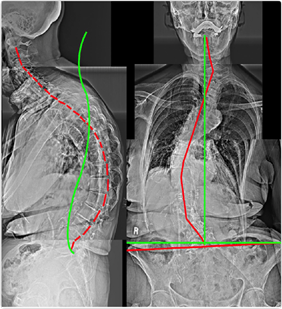

Case 2 — 32yo Female: Chronic Back Pain (6/10)

Figure 2. Scoliosis, Cervical Kyphosis, Thoracic Hypokyphosis, Increased Pelvic Tilt, Lumbar Hyperlordosis. Scoliosis is invisible on physical examination — only visible on AP weight-bearing X-ray.